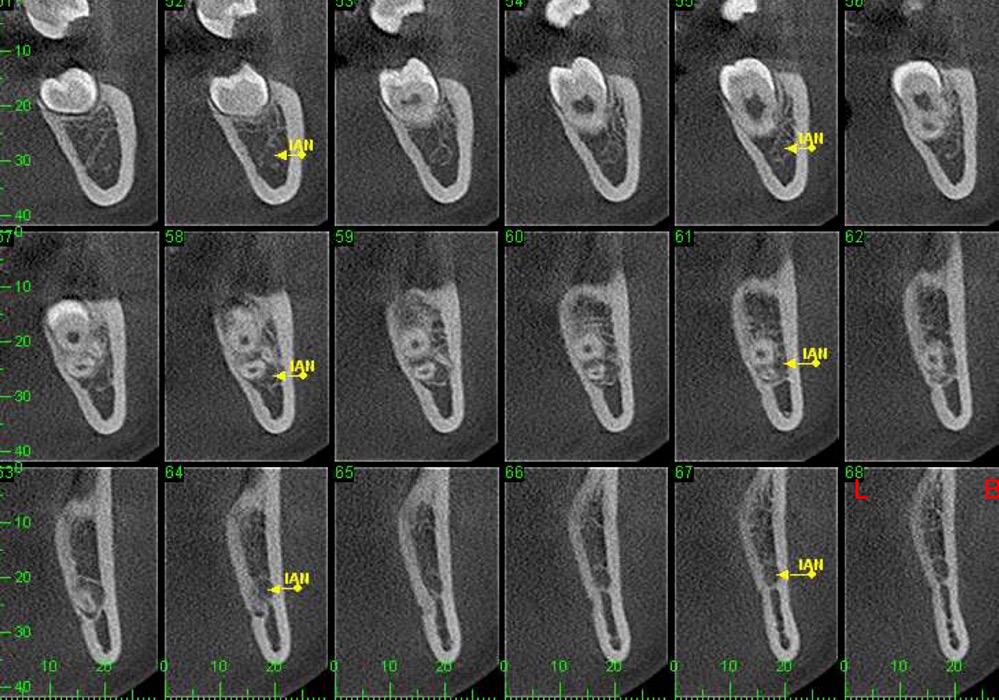

CBCT revealed the following findings:

LL8: IAC was running buccal to roots of LL8 which had 3 roots (Fig 2).

RL8: IAC was seen running between the buccal root which was hooked mesially and lingual roots at its apex, vulnerable to surgical injury (Fig 3).

On discussion with the patient, keeping in mind the clinical and CBCT findings, the option of coronectomy was suggested for LL8 and RL8. If roots become loose during the procedure, then complete removal. The patient consented to have her wisdom teeth removed and coronectomies for the lower wisdom teeth under general anaesthesia.

This case also raises the limitation of the traditional method of imaging with an OPG and shows the importance of CBCT in deciding on the treatment plan. The patient initially visited her dentist in pain with the RL8 and the dentist attempted to remove the tooth to alleviate pain based only on her OPG finding which showed the root apex crossing the upper white line of IAC. Only after referring to a specialist, where CBCT revealed the course of IAC running between the roots of RL8, was the risk of nerve injury avoided.